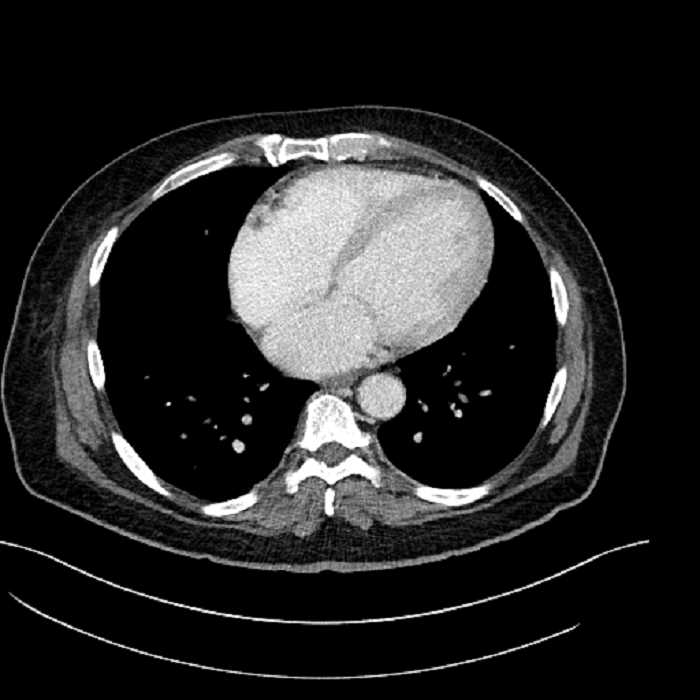

• Lower chest

• Mild cardiomegaly

• Mild dependent atelectasis

Acute sigmoid diverticulitis complicated by a small contained perforation and a large abscess in the right hepatic lobe. Additional small subcapsular abscesses along the anterior margin of the left hepatic lobe.